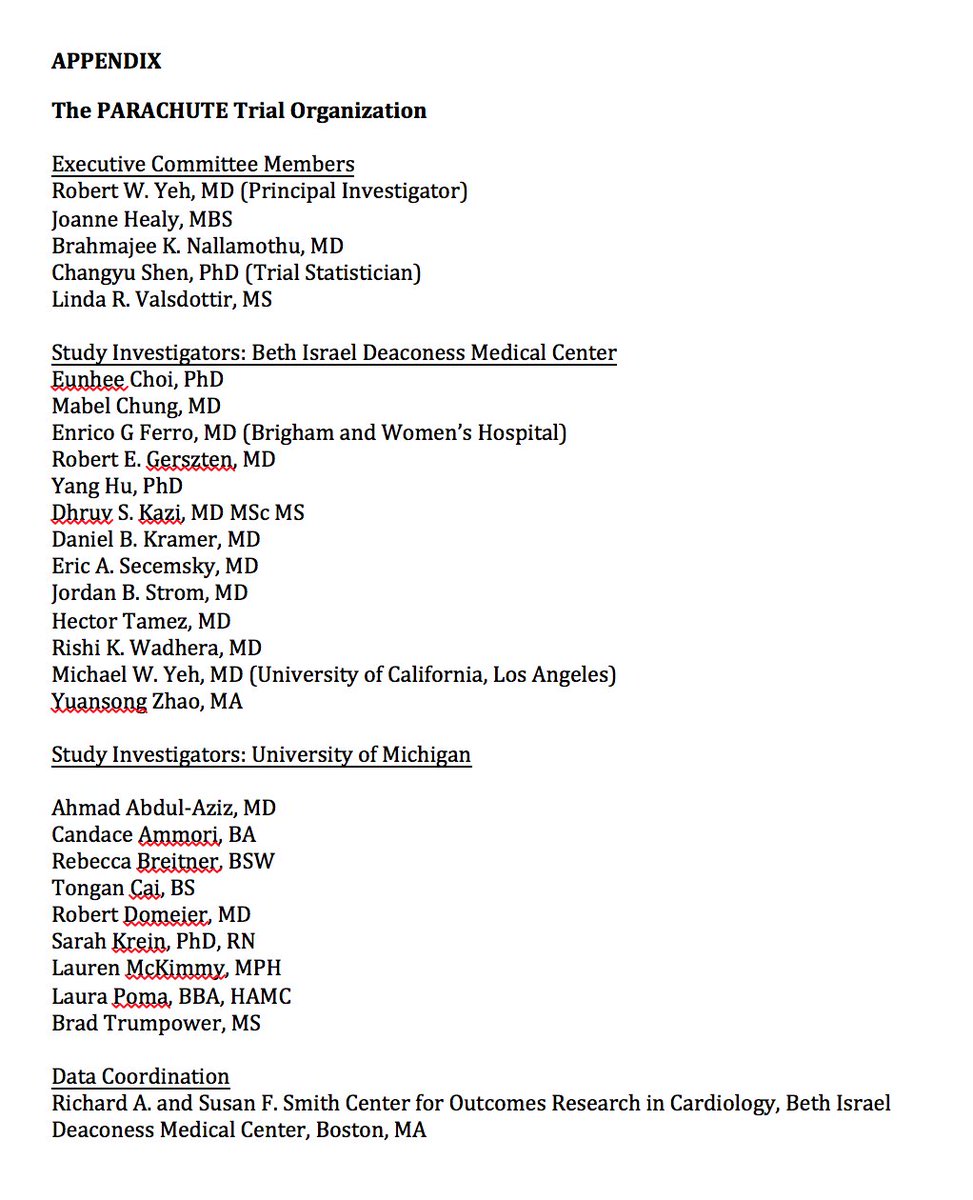

This tweet understates the work and effort

@rwyeh@bnallamo and colleagues at@SmithBIDMC &@UM_MiCHAMP put into making this a reality (it was after all running an RCT). Deeply appreciative for their leadership and efforts to make this happen and for@bmj_latest and their humor.https://twitter.com/rwyeh/status/1073269720680488965 … ಧನ್ಯವಾದಗಳು. Twitter ಇದನ್ನು ನಿಮ್ಮ ಕಾಲರೇಖೆಯನ್ನು ಉತ್ತಮಗೊಳಿಸಲು ಬಳಸುತ್ತದೆ. ರದ್ದುಗೊಳಿಸುರದ್ದುಗೊಳಿಸು

Our newest publication in

@bmj_latest: https://bit.ly/2UFFOFg . Parachute use did not prevent death or major injury in the first RCT of its kind. Happy holidays from@SmithBIDMC@UM_MiCHAMP!@harvardmed@BIDMChealth@michaelyehmd@YuansongZ@ASE360@BIDMCGenCardspic.twitter.com/lzA9OTMH6Z ಈ ಥ್ರೆಡ್ ತೋರಿಸಿಧನ್ಯವಾದಗಳು. Twitter ಇದನ್ನು ನಿಮ್ಮ ಕಾಲರೇಖೆಯನ್ನು ಉತ್ತಮಗೊಳಿಸಲು ಬಳಸುತ್ತದೆ. ರದ್ದುಗೊಳಿಸುರದ್ದುಗೊಳಿಸು